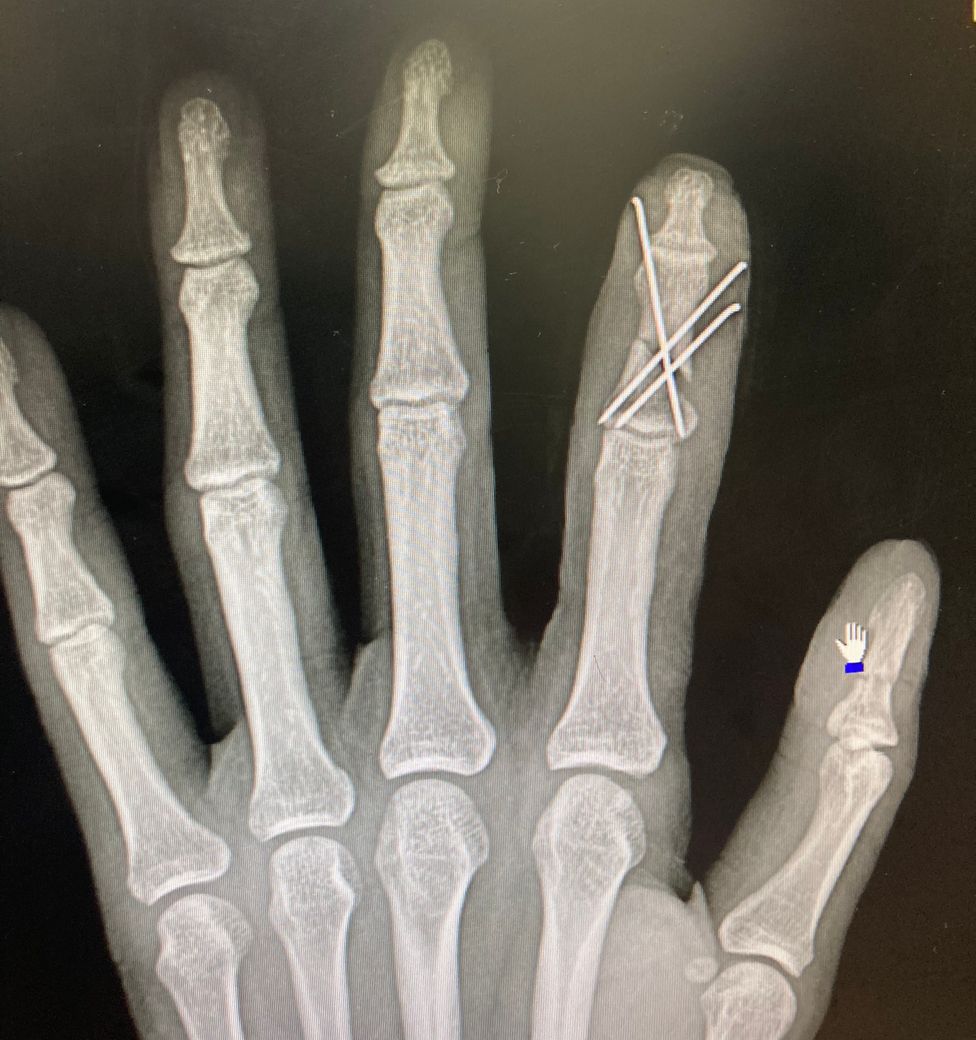

6-7주차 사진입니다 골절 부위가 좀 멀어보이

는데 유합되고있는지 될수있는지

문의드립니다

• 3번 째 사진

수지골 분쇄골절로 k-wire를 하셨네요

아직까지 엑스레이 사진에는 유합소견은 보이지 않는 것 같습니다

개인차이가 있으니 너무 불안해하지 않으셔도 됩니다

벌어져 있는 부분에 골진이 나오면서 점차 차오르고 붙을 겁니다. 지금 상태에서는 회복될 때까지 기다리는 것이 좋을 것 같습니다.